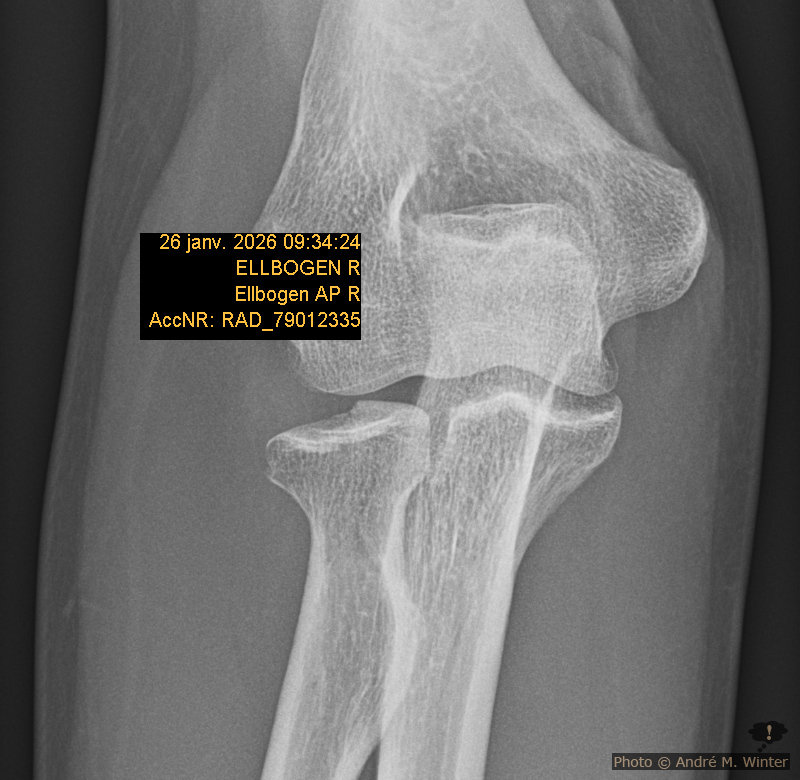

Radiusköpfchen und abgebrochene Stelle

Diesen Versatz sah man dann im zweiten Röntgen, welches mit 45 Grad in den Ellbogen aufgenommen wurde. Der Spalt war grösser als 2 Millimeter, aber nur knapp. Das nennt man fachlich Radiuskopffraktur rechts Mason Typ II. An dieser Grenze wird entschieden ob man eine konservative Verheilung anstrebt oder ob operiert werden muss. Über 2 Millimeter muss normalerweise operiert werden aber es gibt nur um eine par Bruchteile Millimeter darüber. In der Notfallambulanz der Klinik Innsbruck will man die Entscheidung der Handambulanz überlassen und man verpasst mir einen Spaltgips von der Hand bis zur Schulter über den Rest des Wochenendes. Der Spalt bedeutet nicht dass er abnehmbar ist, er ist bloss ein wenig leichter. Ich war ganze 6 Stunden dort. Aber auch mühsam verletzte (Schulterbruch) liess man so lange warten.

Röntgen Ellbogen nach fünf Wochen nach dem Unfall